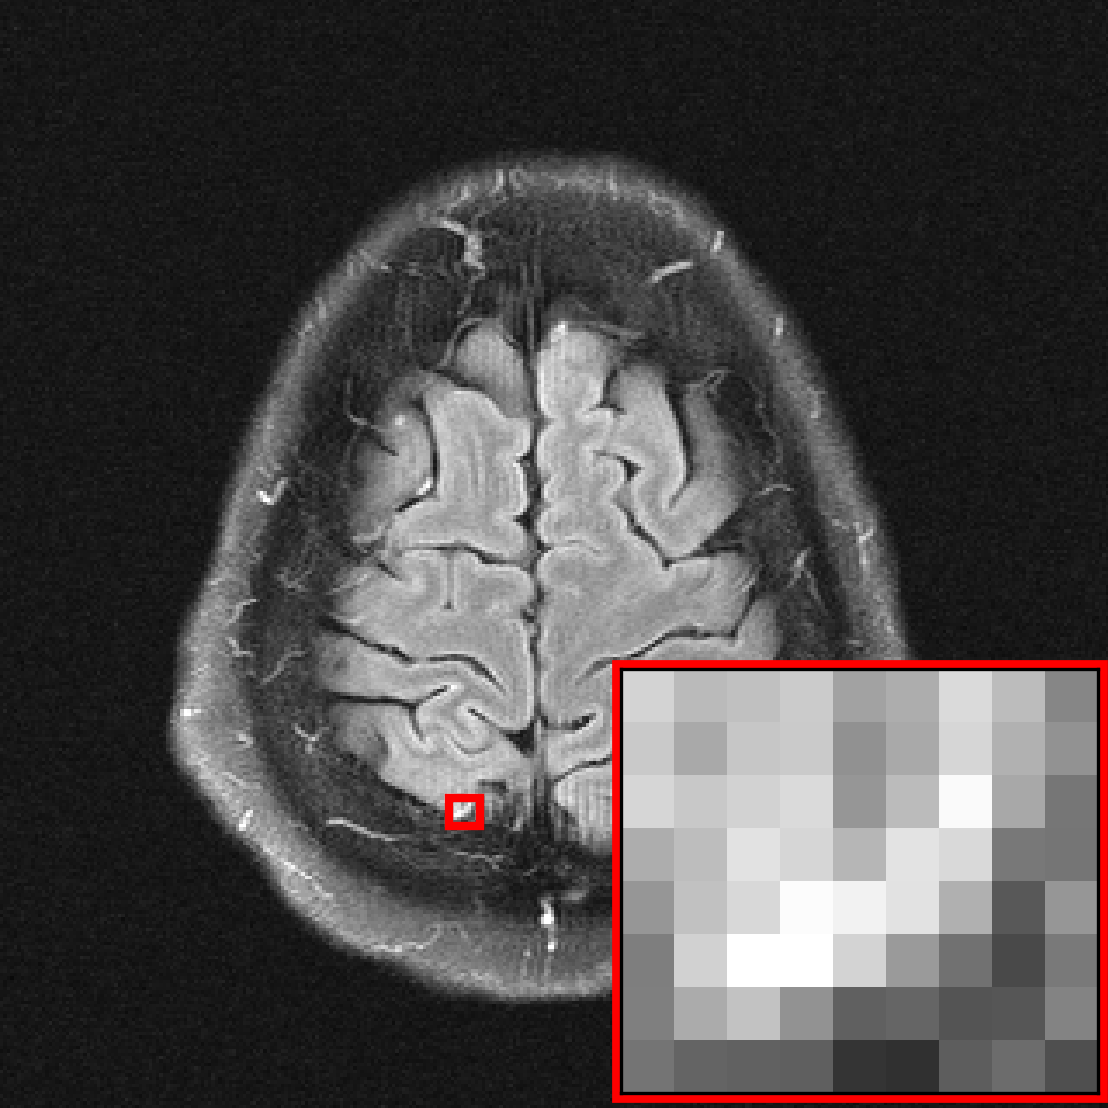

![[Uncaptioned image]](extracted/5298803/figs/pathology/lacunar_infarct_out_varnet.png)

![[Uncaptioned image]](extracted/5298803/figs/pathology/mass_out_varnet.png)

![[Uncaptioned image]](extracted/5298803/figs/pathology/lacunar_infarct_out_varnet_bl.png)

![[Uncaptioned image]](extracted/5298803/figs/pathology/mass_out_varnet_bl.png)

![[Uncaptioned image]](extracted/5298803/figs/pathology/lacunar_infarct_ref.png)

![[Uncaptioned image]](extracted/5298803/figs/pathology/mass_ref.png)

In this section, we investigate the distribution shift from healthy to non-healthy subjects by measuring how well models reconstruct images containing a pathology if no pathologies are contained in the training set. We find that models trained on fastMRI data without pathologies reconstruct fastMRI data with pathologies equally well as the same models trained on fastMRI data with pathologies.

We see that the models trained on show essentially the same performance (SSIM) as models trained on regardless of pathology size. The results indicate that models trained on images without pathologies can reconstruct pathologies as accurately as models trained on images with pathologies. This is further illustrated in Figure 6 (and Figure 16), where we show reconstructions given by the VarNet of images with a pathology: the model recovers the pathology well even though no pathologies are in the training set. Figure 14 in the appendix provides a more nuanced evaluation of the SSIM values for VarNet.